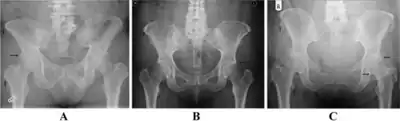

a-c) Grade 1,2, and 3 of pelvic radiographs of enthesophytes